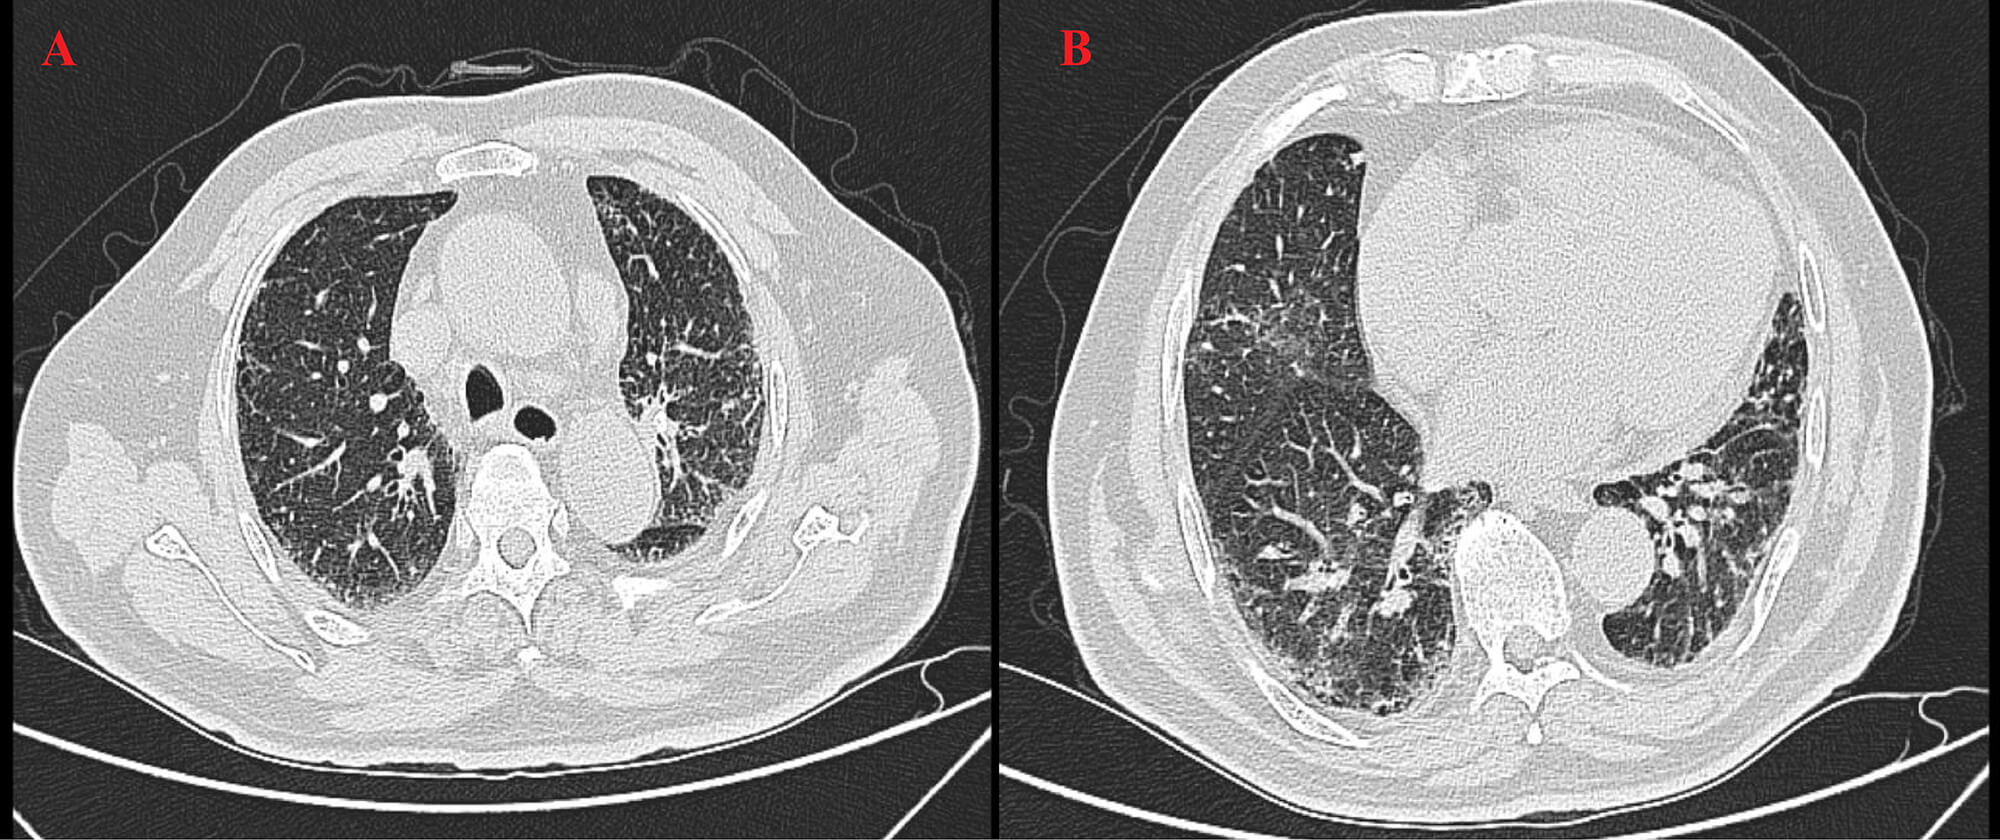

High-resolution computed tomography (HRCT) (Fig. 3) revealed patchy opacities in the left upper and right lower lobes, accompanied by multiple enlarged hilar and mediastinal lymph nodes (Fig. 4), interstitial inflammation in both lungs (Fig. 5), and a small pleural effusion. These findings were consistent with residual tumor and local progression following treatment for extensive-stage SCLC, demonstrating characteristic imaging features of SCLC.

Fig. 4.

HRCT on 6 May 2025. (A) The left upper lobe shows a patchy high-density shadow with interstitial changes, indicating post-treatment inflammation and tumor activity. (B) The right lower lobe shows consolidation with diffuse interstitial thickening and mediastinal lymphadenopathy, suggesting inflammatory progression.